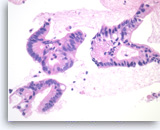

Ductal adenocarcinoma #1,

Pancreas FNA, Cell Block.

The tumor cells are pleomorphic and form poorly organized glands of variable sizes. Some of the glands are fused together. Prominent intracytoplasmic mucin is present.

40X